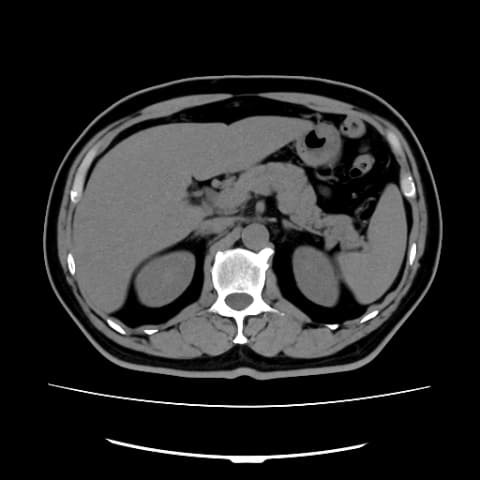

chocoZAP(チョコザップ)でMRI検査/CT検査/エコー検査を受けられることをご存知でしょうか。24年5月に始まったchocoZAPメディカルの「Mini人間ドック[MRI・CT・エコー]」というサービスで、新宿にあるchocoZAPの提携医療機関で受けられます。

chocoZAP会員であれば年に1回、追加料金なしで検査ができるのが大きな特徴。実際にchocoZAPメディカルでCT検査を体験したので、その様子をレポートします。

Mini人間ドックで受けられるのは、MRI(頭部)、CT(胸部または腹部)、エコー(乳腺または腹部)、いずれか最大年1回まで受検でき、サイトから予約を行ないます。追加で検査したい場合は、1回につき5,000円で利用することも可能です。検査は最短15分程度で完了し、結果は後日電子データのレポートで受け取れます。

CT検査を体験した

実際にchocoZAPメディカルでCT検査を体験してみました。chocoZAPメディカルは新宿三丁目のchocoZAPに併設されており、検査前後でchocoZAPでトレーニングすることも可能です。

ちなみに筆者は腹部CT検査だったので検査前6時間の絶食が必要となり、予約が13時だったので朝食を7時までに済ませていました。朝起きるのが苦手、しっかり食べてから行きたい場合は午後遅めの時間で予約したほうが良さそうです。なおMRIと胸部CTは検査前の食事制限はありません。

番号で呼ばれたら荷物をロッカーに預け検査室に入ります。スタッフの指示に従い、検査台に横になったら指示に従って呼吸をし、5分ほどで検査が完了しました。CTは5~10分、頭部MRIは15分ほどで終わるそうです。